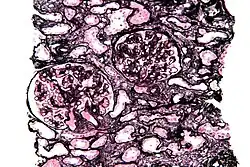

Jones' stain

Jones' stain, also Jones stain, is a methenamine silver–periodic acid–Schiff stain used in pathology.[1] It is also referred to as methenamine PAS which is commonly abbreviated MPAS.

It stains for basement membrane and is widely used in the investigation of medical kidney diseases.

The Jones stain demonstrates the spiked GBM, caused by subepithelial deposits, seen in membranous nephropathy.